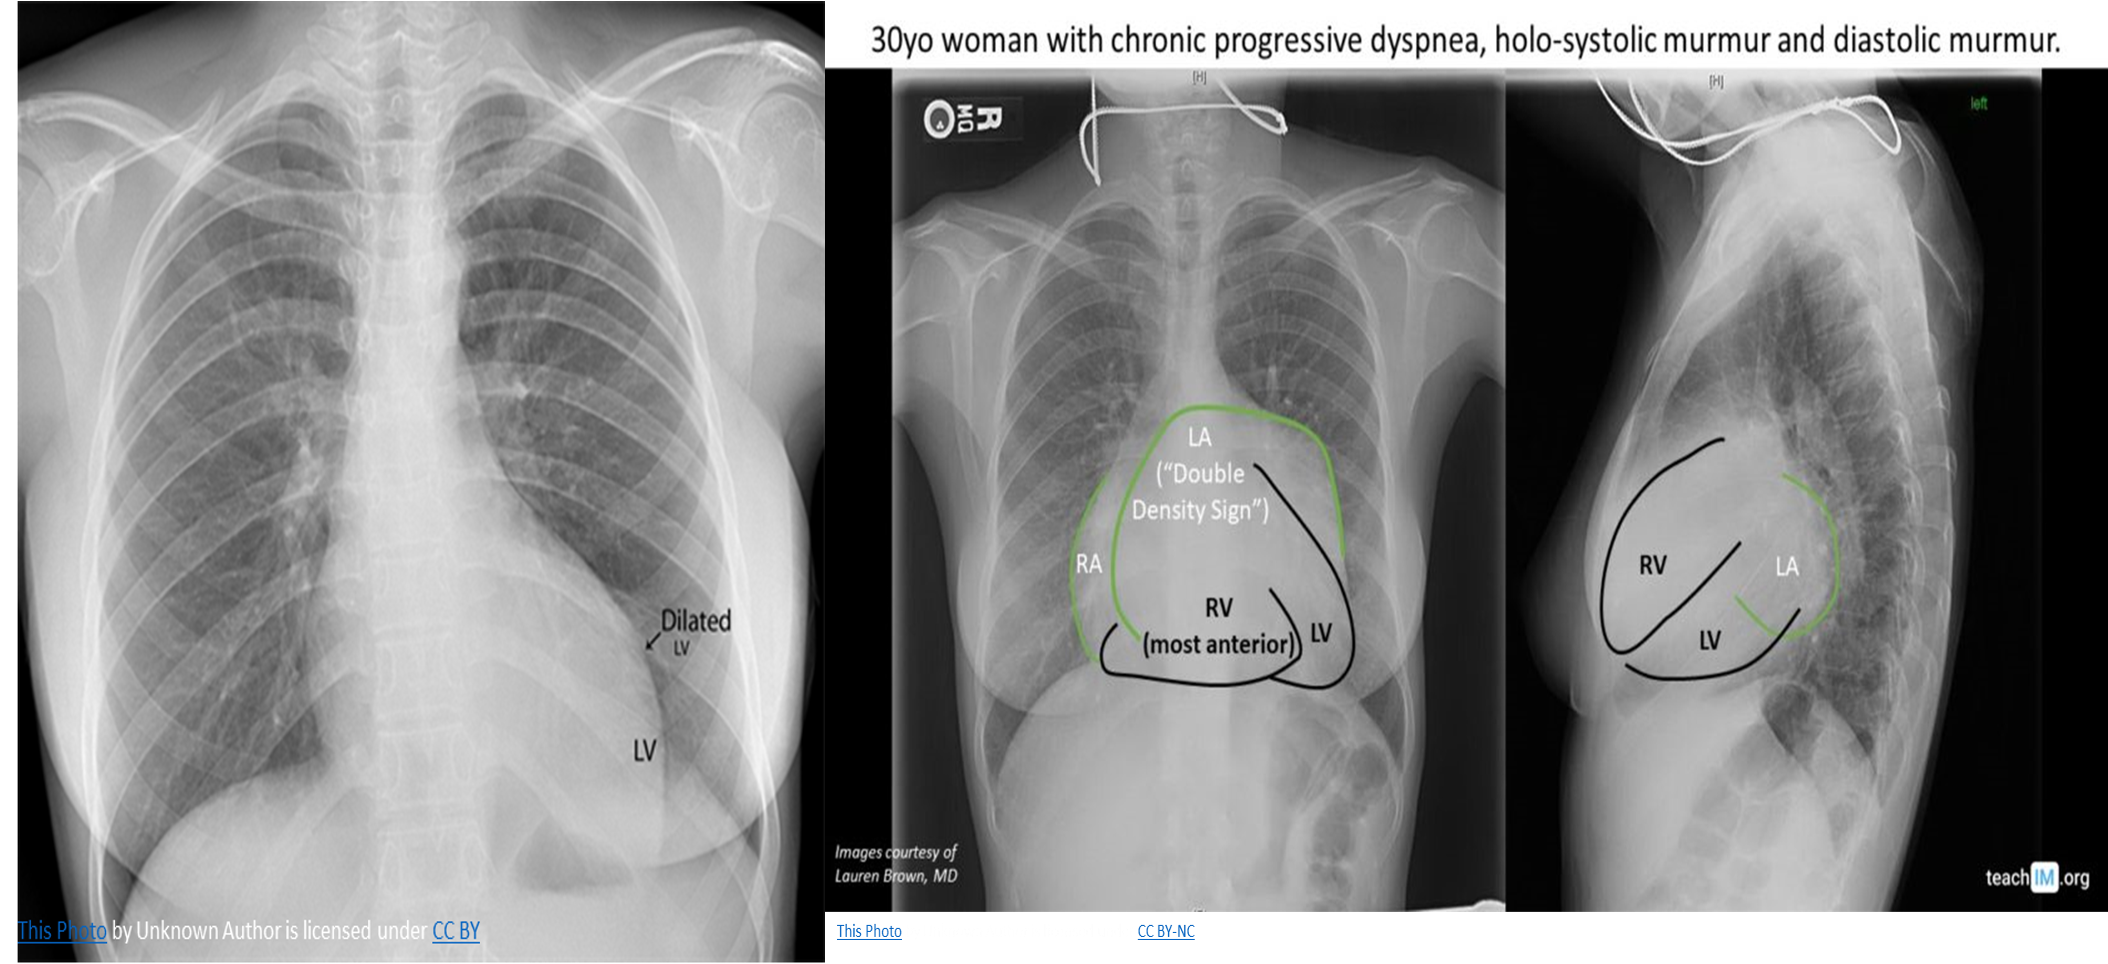

CXR

Cardiomegaly: enlarged left atrium and ventricle

-

Signs of congestive heart failure

Acute MR: heart size is usually normal but shows pulmonary edema (alveolar edema).